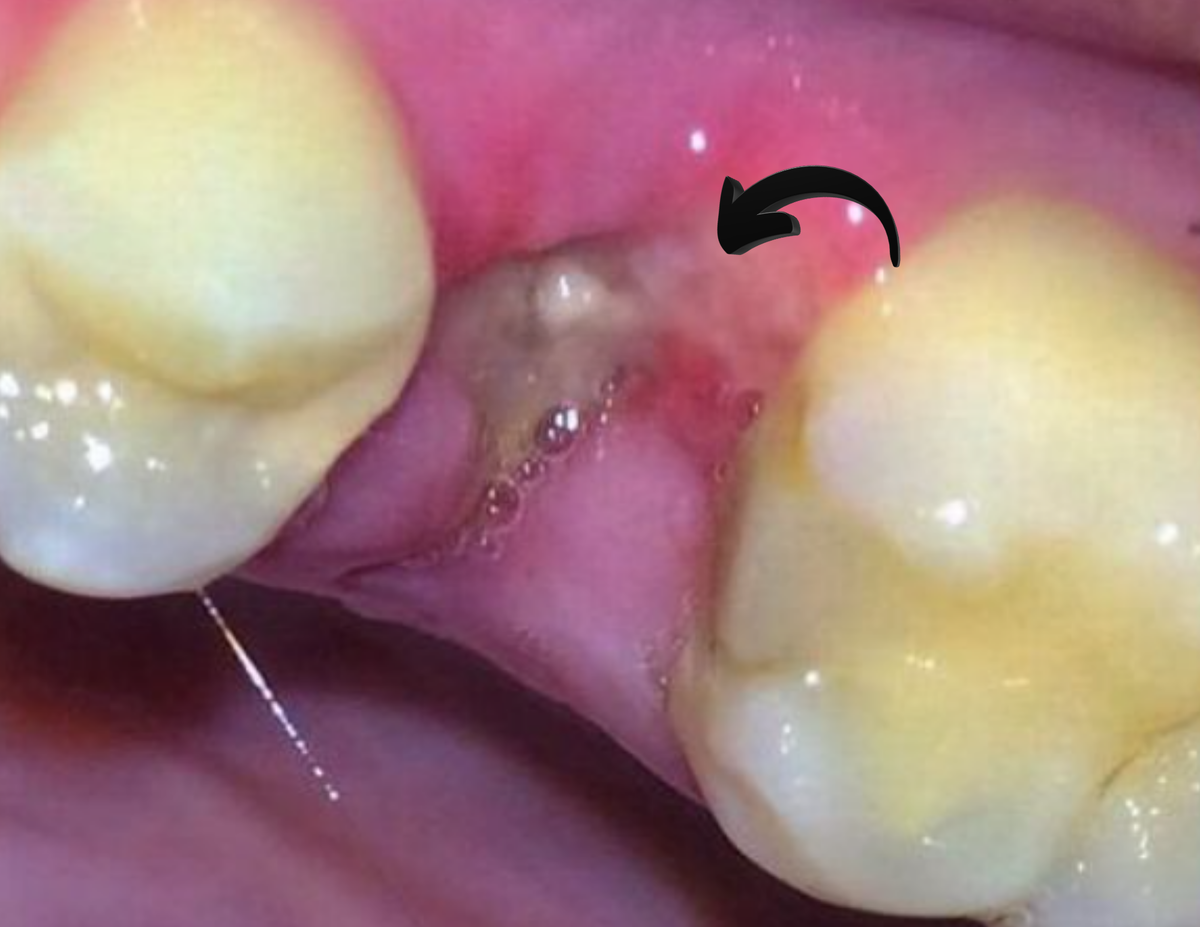

Внешний вид лунки

После нормального удаления лунка заполняется кровяным сгустком. Он тёмно-красный, плотный и немного западает внутрь. Этот сгусток защищает костную ткань от слюны, пищи и бактерий.

При альвеолите сгустка почти не бывает. Лунка выглядит пустой. Может виднеться сероватый или желтоватый налёт, иногда виден костный край. Почти всегда есть запах - тухловатый, ненавязчивый, но ощутимый.

Это и есть сухая лунка. Сгусток вымылся раньше времени или вообще не сформировался. Кость открыта - воспаление развивается быстро.

Иногда пациенты видят то, чего на самом деле нет, принимая за сгусток желтоватую грануляцию или пищевые остатки. Ориентир прост: нормальный сгусток плотный, тёмный и упругий. Если в лунке что-то рыхлое, светлое и легко смывается слюной - это не сгусток. Это признак того, что процесс уже идет.